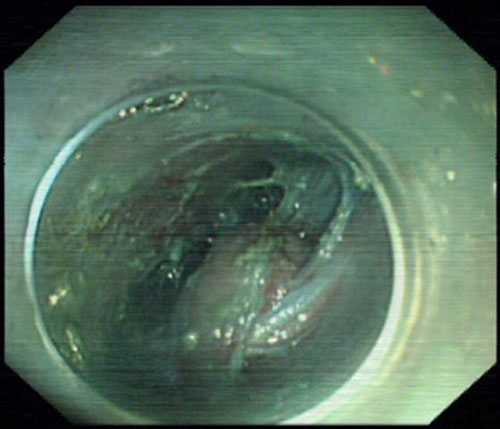

在肿瘤上方5cm建立隧道入口

内镜于隧道内见肿瘤

2013年11月18日下午,经精心准备,在内镜中心麻醉呼吸机辅助全麻下,杨力主任运用内镜微创切除器械,于肿瘤上方5cm的食管黏膜纵向切开后,沿食管黏膜下层至肿瘤开辟了一条粘膜下“隧道”, 胃镜于“隧道”内直视下切除肿瘤,再用金属钛夹封闭食管表层的粘膜切口,历时65分钟顺利完成手术,术后第3天进流食,7天后患者康复出院,